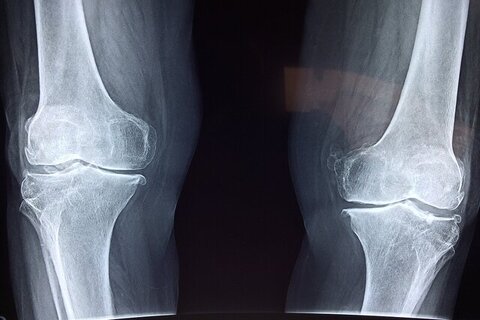

محققان یک سیستم تشخیصی مبتنی بر هوش مصنوعی توسعه داده‌اند که می‌تواند تراکم مواد معدنی استخوان را هم در ستون فقرات کمر و هم در استخوان ران پا، بر اساس تصاویر اشعه ایکس تخمین بزند.

به گزارش ایراسین به نقل از ایسنا، در مجموع ۱۴۵۴ تصویر اشعه ایکس با استفاده از سیستم دانشمندان مورد تجزیه و تحلیل قرار گرفت. میزان حساسیت عملکرد برای کمر و استخوان ران بیماران مبتلا به کاهش تراکم استخوان به ترتیب ۸۶.۴ و ۸۴.۱ درصد بود.

به نقل از مدیکال‌اکسپرس، میزان اختصاصی بودن آن نیز ۸۰.۴ و ۷۶.۳ درصد بود. حساسیت، توانایی آزمایش در شناسایی صحیح افراد مبتلا به پوکی را نشان می‌داد در حالی که اختصاصی بودن، توانایی آن را در شناسایی صحیح افراد بدون پوکی استخوان نشان می‌داد. این آزمایش همچنین از حساسیت و اختصاصی بودن بالایی برای دسته‌بندی بیماران مبتلا به پوکی استخوان و بدون آن برخوردار بود.

دکتر تورو مورو، نویسنده مسئول این مقاله از دانشگاه توکیو، می‌گوید: اندازه‌گیری تراکم مواد معدنی استخوان برای غربالگری و تشخیص پوکی استخوان ضروری است، اما دسترسی محدود به تجهیزات تشخیصی به این معنی است که میلیون‌ها نفر در سراسر جهان ممکن است از این بیماری بی‌اطلاع بمانند.

این سیستم هوش مصنوعی پتانسیل تبدیل عکس‌های رادیولوژی بالینی معمول را به ابزاری قدرتمند برای غربالگری دارد و امکان تشخیص زودهنگام، گسترده‌تر و کارآمدتر پوکی استخوان را فراهم می‌کند.